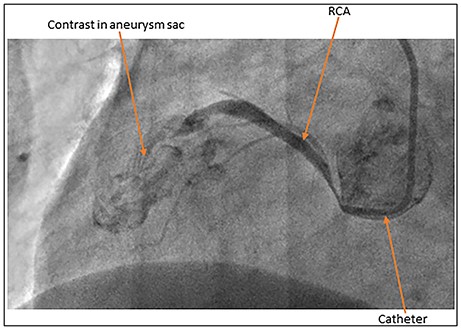

Coronary artery angiogram showing extravasation of contrast into the aneurysm sac.

Coronary angiogram demonstrated a normal left main stem, disease in the mid-left anterior descending artery and a minor atheroma in the left circumflex artery. The RCA was seen to be filling only to the mid-segment, as shown in Fig. 1, after which the contrast extravasated suggesting a possible aneurysm. No pericardial effusion was seen. Aortogram showed no obvious dissection flap.